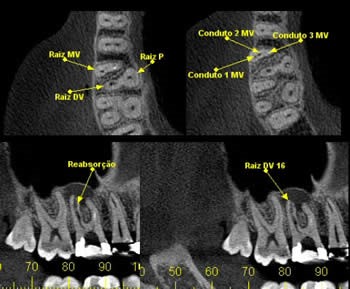

Novas tecnologias, instrumentos e materiais conduziram a um melhor diagnóstico e a uma maior previsibilidade do tratamento endodôntico. A Tomografia Computadorizada por Feixe Cônico (TCFC) tem um papel importante no diagnóstico e planejamento destes tratamentos, pois permite uma visualização 3D e elimina as sobreposições de estruturas.

A Tomografia Computadorizada passa a auxiliar no tratamento endodôntico, no planejamento pré-cirúrgico, na identificação da morfologia e anatomia dos canais, na detecção de canais não visíveis ou acessórios, na realização de medições precisas das distâncias dos canais, na avaliação das fraturas ou traumas das raízes, nas análises e caracterização externa e interna das reabsorções radiculares assim como de reabsorções cervicais, na deteção da diferença entre cistos e granulomas ou ainda em outros tipos de lesões de cavidade.

A morfologia das raízes e a topografia óssea podem ser observadas na renderização 3D das imagens, assim como o número de canais radiculares, a sua divergência ou convergência, o seu verdadeiro tamanho, localização e extensão das lesões periapicais e a qual a raiz existe uma lesão associada.

Desta forma, podemos concluir que a TCFC conduz a um melhor planejamento da cirurgia endodôntica, levando a uma melhoria dos resultados e objetivos. A seguir, para ilustrar, apresentamos alguns casos, onde podemos evidenciar a utilização da TCFC: